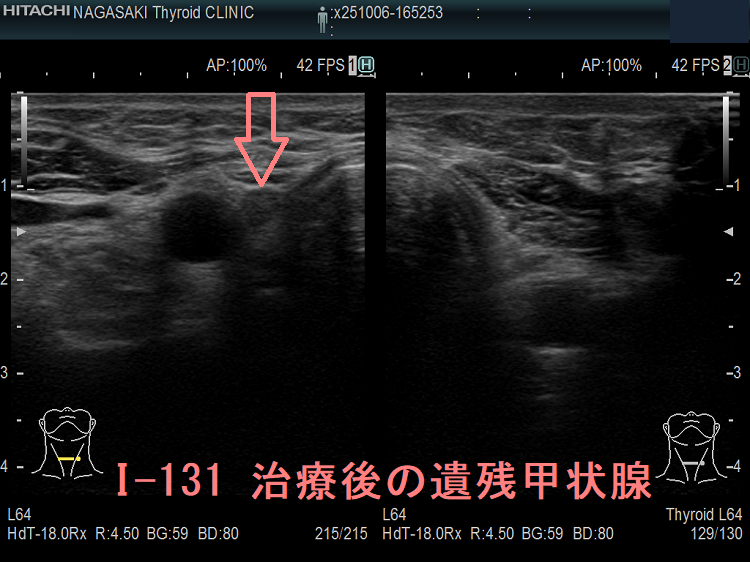

I-131 治療後の遺残甲状腺

甲状腺癌全摘出に続くI-131 治療後の超音波(エコー)画像。元々、副甲状腺を温存する目的で、右葉が僅かに残っていますが、I-131 治療によって正常な甲状腺濾胞細胞は消滅しているはずです。